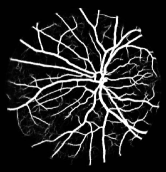

Refer to caption

Figure 1: Vessel segmentation results of side-output(s-out) layers produced by three networks. From top to bottom the network is normal DSN (with no short connections), BS-DSN (DSN with bottom-top short connections) and BTS-DSN (DSN with both bottom-top and top-bottom short connections), respectively.

As pointed out in recent works [15, 17], a good semantic segmentation network should learn multi-level features. Further, it should have multiple stages with different receptive fields to learn more inherent features from different scales. FCN, taken as an example, uses skip connections to fuse multiple stages outputs, as well as the HED network, in which a series of side-output layers are added after each stage in VGGNet. The HED network was first proposed for edge detection, and further used for image-level vessel segmentation in recent studies [6, 16], with significant performance. However, our experimental results show that such network architecture is not appropriate for vessel segmentation directly. Figure 1 provides such an illustration. Reasons for this phenomenon are straightforward. On one hand, the side-output of the first layer often contains too many noises. On the other hand, the features produced by the last side-output layer are too coarse due to information loss of pooling operation. Obviously, the inaccurate vessel map of side-output1 and side-output4 should have negative impacts on the final segmentation result.

In addition, we can observe from Figure 1 that the side-output1 and side-output4 of the BTS-DSN were more accurate compared with those of the DSN.